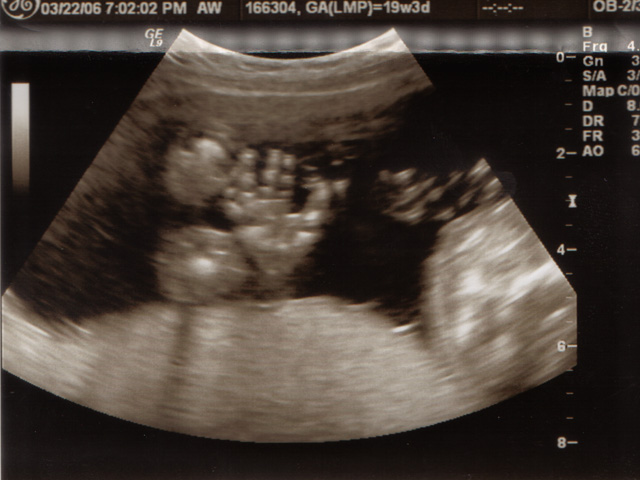

My sonograms.

<Click on the photo for a larger view>